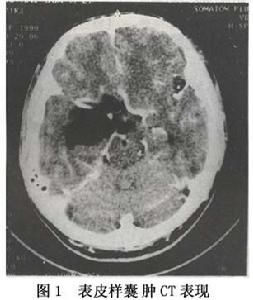

2.CT 表皮樣囊腫在CT上的典型影像特徵為均勻低密度區,CT值在-2~12Hu之間低於腦脊液值,形態不規則,多為孤立,有占位效應。強化掃描一般無明顯增強。Nosaka(1979)報告1例右腦橋小腦角原發性上皮癌,並複習文獻13例,強化掃描影像增強並認為腦橋小腦角為表皮樣囊腫惡性變的常見部位,占57.1%。